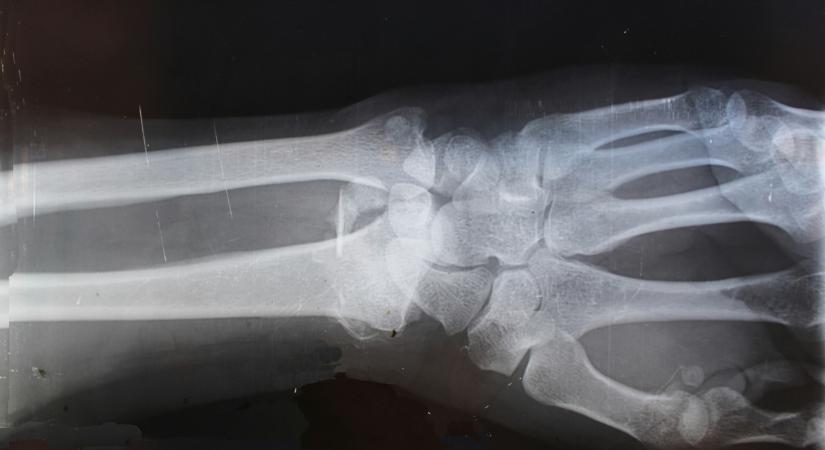

Te törted már el valamidet? Vészjósló dologra utalhat, ha nem